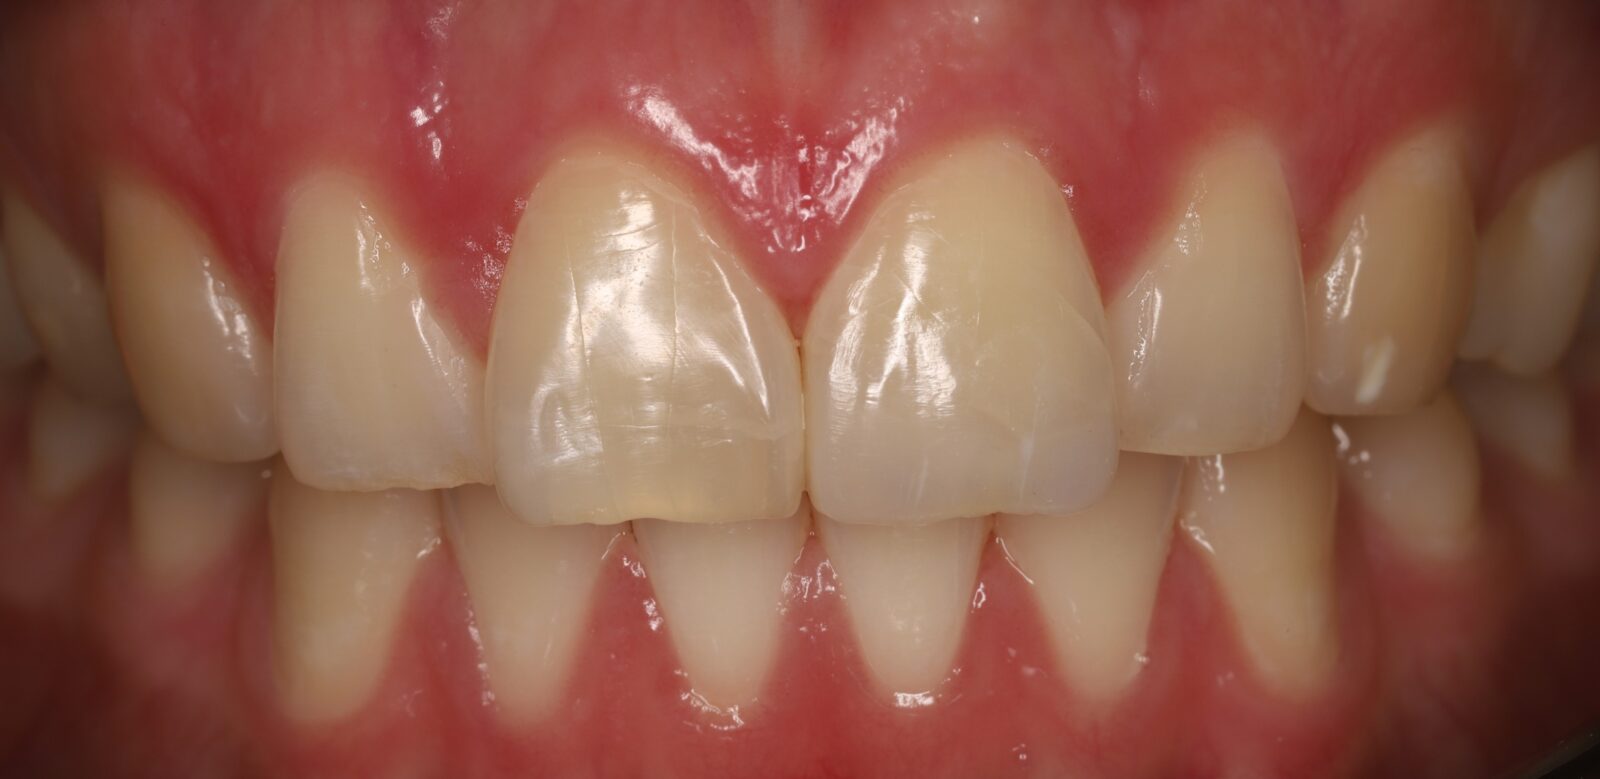

Внутриротовые фотографии 17.10.2022г

Спустя 6 месяцев после травмы окончательно отреставрировали 2.1 зуб. (фото после снятия коффердама, пациент больше не явился на осмотр)

Спустя 6 месяцев после травмы. (белая полоска около десны вследствие лечения в коффердаме)

Наблюдение: Фотографии спустя 1 год и 8 месяцев. 22.06.2024г.

Была проведена незначительная корректировка и отполировали до блеска